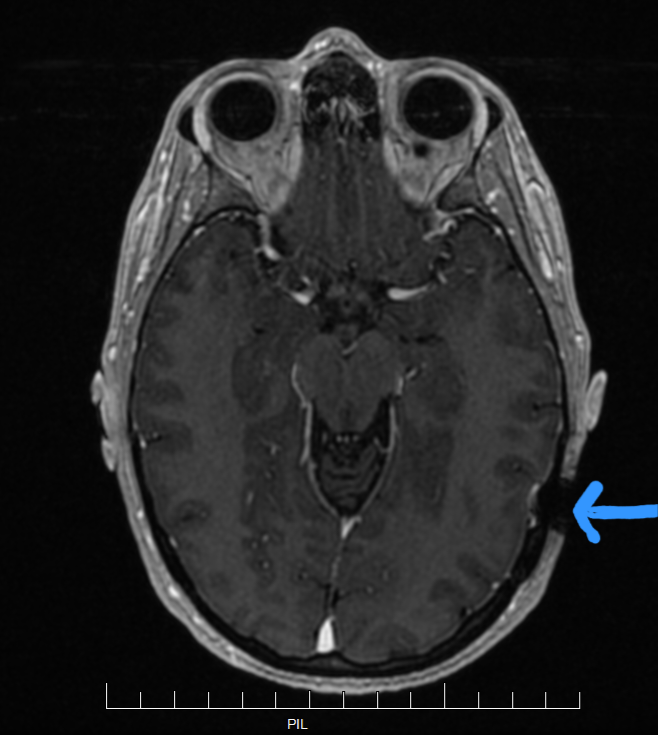

In contrast, this is my most recent MRI. The shadow from my Ponto abutment is the small black circle in the lower right side of the image. It definitely does not stop me from getting useful data from my MRIs.

I would definitely shy away from getting an implanted style bone anchored device if I believed regular brain MRIs were important for my health, such as montioring brain tumor growth. At minimum, I definitely recommend searching to find out MRI implications for any device you are considering. I think John’s story is really unfortunate. The doctors and hearing device companies should be forthright about the pros and cons of these devices.